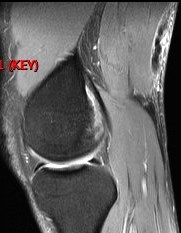

46 y/o male. Injury doing sprints. Posterior thigh pain. Hamstring injury.

Figure 1 for case Semitendinosus tendon tear, retracted( RID2717 )

Semitendinosus tendon tear, retracted( RID2717 )